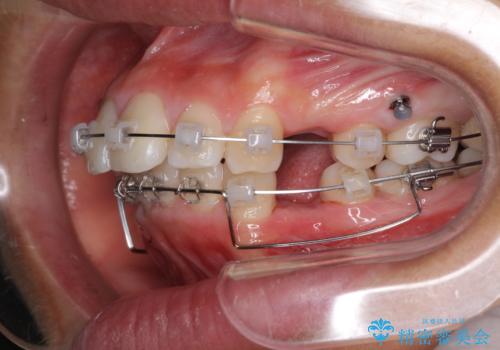

- クリアブラケット

口元を積極的に引っ込めるために、上下左右の第一小臼歯を4本抜歯することとしました。

途中で来院されない時期があったため、期間が長引き、更には磨き残しが多かったことで虫歯が多く発現してしまいました。